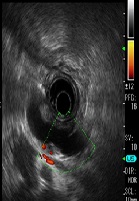

Pancreatic Duct Drainage Using EUS-Guided Rendezvous Technique for Dilated Pancreatic Duct due to the Stenosis of Anastomotic after Pancreaticogastrostomy: A Case Report

Ai Jia, Goro Shibukawa, Ai Sato, Akane Yamabe, Takumi Maki, Yoshitsugu Yoshida, Shogo Yamamoto, Ryo Igarashi, Yuki Nakajima, Atsushi Irisawa*